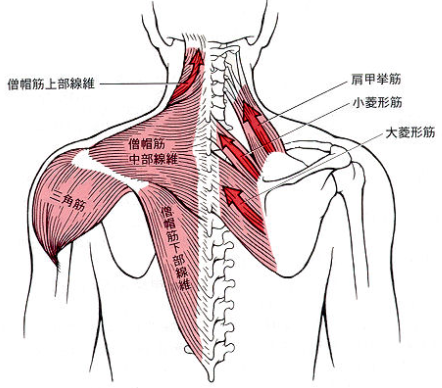

僧帽筋上部、三角筋、肩甲挙筋、小菱形筋、棘上筋、棘下筋、烏口腕筋、上腕二頭筋長頭・短頭、肩甲下筋、前鋸筋

の圧痛が徐々に緩和。

肩関節外転で三角筋、上腕二頭筋長頭・短頭、烏口腕筋

が特に運動痛著明。

腕を横に挙げていき、60度を過ぎると、肩甲骨が動いて行かないと腕は挙がりません。僧帽筋の深層にある肩甲挙筋の収縮と菱形筋の伸展(柔軟性)が欠かせません。しかし、それだけではなく、動き初めには棘上筋がまず動きますが、小さな筋肉で血流が停滞して炎症が出やすい筋肉です。

さらに、大胸筋、小胸筋、上腕二頭筋、烏口腕筋が短縮しやすく、疲れ、痛みが出やすい筋です。